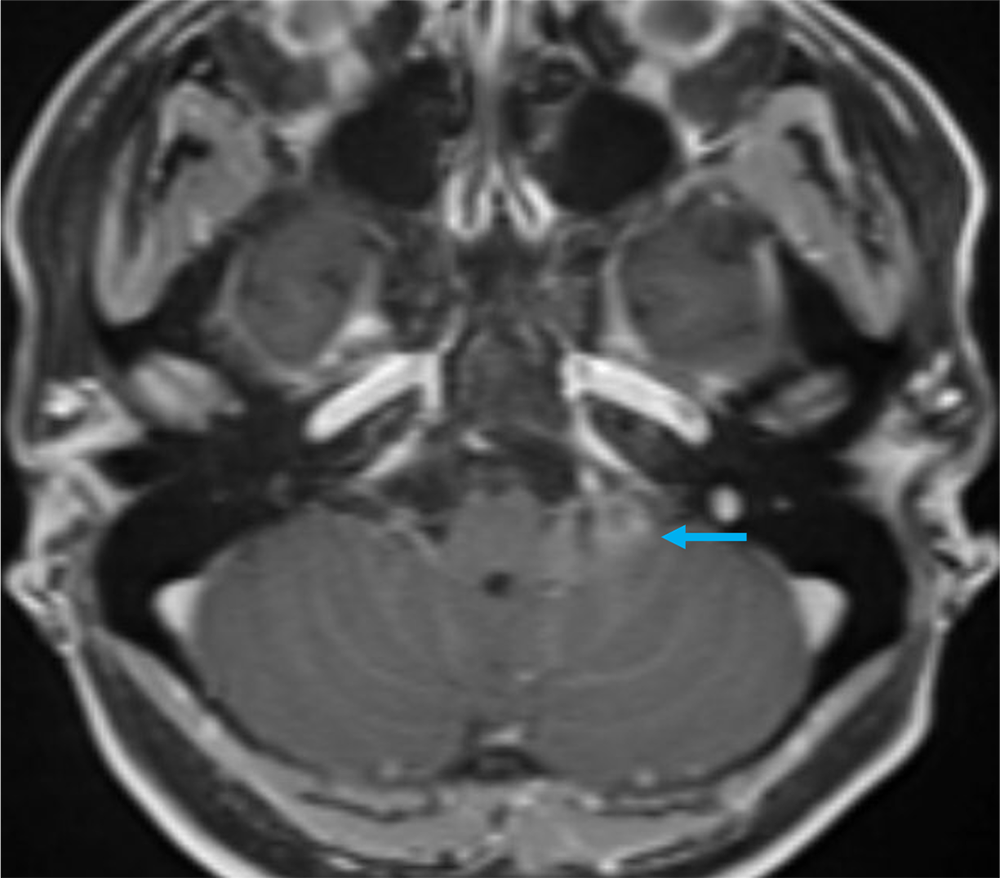

40歳代、女性、55kg、pilocytic astrocytoma

2か月前から頭重感および嘔気が持続しており、他院の単純CTにて左小脳腫瘍が疑われた。当院紹介となり、造影MRIが撮影された。

本症例では左小脳延髄角部に嚢胞成分を伴う腫瘍が存在し、左下位脳神経からの発生、もしくは小脳実質内腫瘍の鑑別が重要であった。前者であれば神経鞘腫、後者であればpilocytic astrocytomaの可能性が高くなる。3Dの脂肪抑制T1強調画像を撮影し、小脳実質内の可能性が高く、pilocytic astrocytomaを上位に考えた。手術が施行され、無事に完全摘出され上記の診断となった。

当該疾患の診断における造影MRIの役割

小脳腫瘍の鑑別において、造影MRIは必須である。本症例のように若年者の小脳実質内腫瘍の場合、特に血管芽腫との区別が重要となる。血管芽腫も嚢胞成分を伴う腫瘤を呈することが多いが、充実成分は強い造影効果を呈する。本症例は血管芽腫を疑うような強い造影効果とは言えず、pilocytic astrocytomaを疑うことが可能であった。